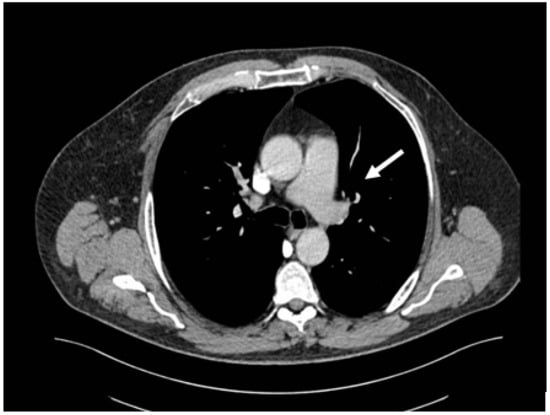

Figure 1. CT pulmonary angiography—pulmonary embolism, thrombus on the left main pulmonary artery (white arrow).

Out of the 13 patients, 3 patients had PE without evidence of DVT (0.60% of the total patients included in the study) (Figure 1).

Duplex ultrasonography is widely accepted as the primary diagnostic procedure for the evaluation of suspected deep vein thrombosis and is also commonly used for follow-up assessments to monitor the response to anticoagulant therapy or to identify the progression of DVT. CT pulmonary angiography (CTPA) has become the primary imaging modality for diagnosing pulmonary embolism due to its high sensitivity and specificity. It provides detailed and cross-sectional images of the pulmonary vasculature. Although a CT scan may not be very accurate in detecting small peripheral emboli, it is capable of revealing various structures in the thorax, providing a comprehensive view of the chest area, and can reveal conditions other than thromboembolism, assisting in identifying alternate diagnoses [15].

The diagnosis of DVT was made in our burn center using duplex ultrasound at the patient’s bedside, with a focus on clinically symptomatic patients presenting with increased limb edema or pain. All patients with DVT underwent screening for PE. CT pulmonary angiography was used for the diagnosis of PE, providing an assessment of the location and degree of clot burden. In every patient diagnosed with DVT, weekly ultrasound examinations were conducted to monitor the size and evolution of the thrombus under treatment.